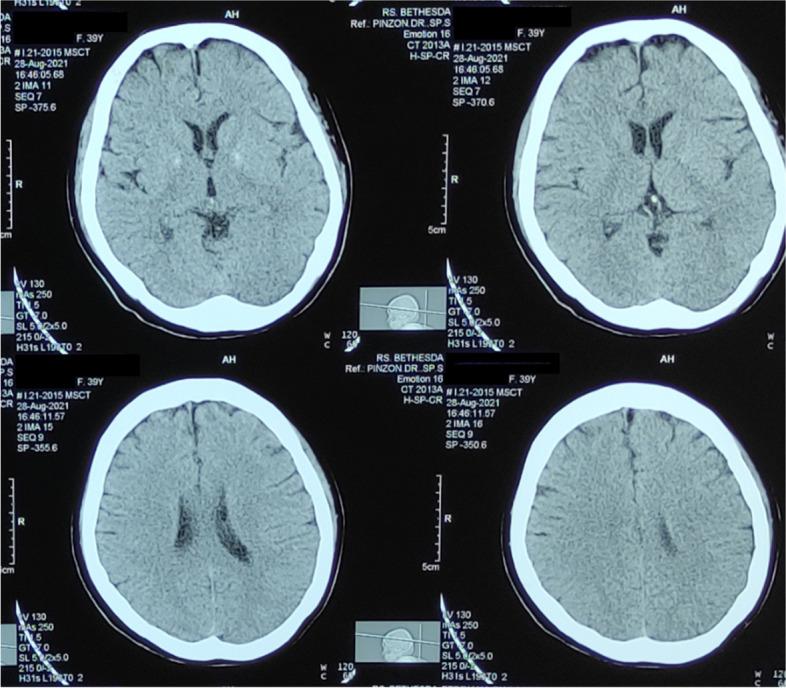

We describe a 39-year-old female with uncontrolled hypertension who showed behavioral change, communication difficulty, social withdrawal, and a confused state within 7 days from getting her first dose of the Moderna vaccine. The patient had a history of febrile convulsion in childhood. An increase of neutrophil-to-lymphocyte ratio (16.9) and C-reactive protein level (31.75 mg/L) indicates ongoing inflammation. Head CT scan shows no abnormalities. She received ceftriaxone, citicoline, and methylprednisolone. The patient was discharged on the seventh day and completely recovered 1 week later. This study is the first case report of encephalopathy following the administration of the Moderna COVID-19 vaccine reported in Indonesia up to our knowledge.

我们描述了一名 39 岁的女性,患有未控制的高血压,在接种 Moderna 疫苗第一剂后 7 天内出现行为改变、沟通困难、社交退缩和意识混乱。患者在儿童时期有热性惊厥病史。中性粒细胞与淋巴细胞比值(16.9)和 C 反应蛋白水平(31.75mg/L)升高表明存在持续炎症。头部 CT 扫描未见异常。她接受了头孢曲松、胞磷胆碱和甲基强的松龙治疗。患者在第 7 天出院,1 周后完全康复。据我们所知,这是印度尼西亚首例报告接种 Moderna COVID-19 疫苗后发生脑病的病例。